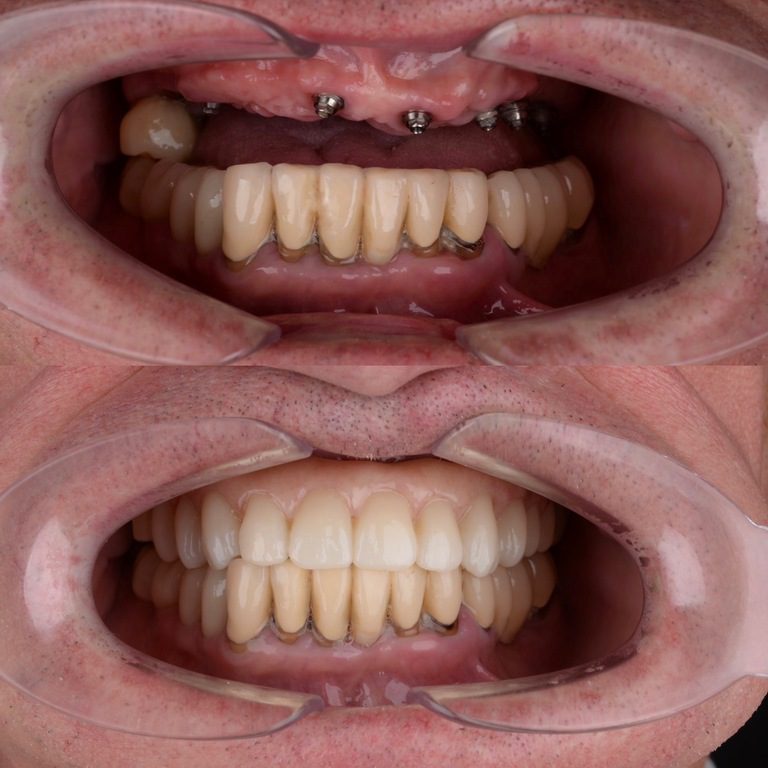

Our cases

PROSTHETICS

Restore a tooth or a whole line of them with help of modern methods and high quality materiel

Remove teeth, we carry out plastic surgery of soft and bone tissues, install imlpants and other